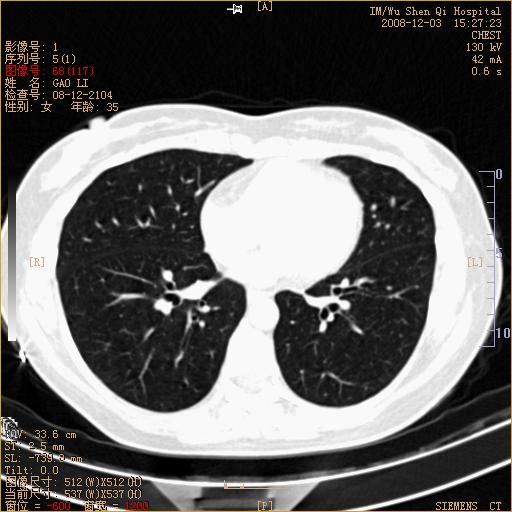

标题: CT16895:女,35岁,反复咳嗽数月,只传部分图像,是否考虑 [打印本页]

标题: CT16895:女,35岁,反复咳嗽数月,只传部分图像,是否考虑

左下肺支扩

典型“印戒征”。

印戒征,支持支扩.

左下肺扩支

印戒征,支扩